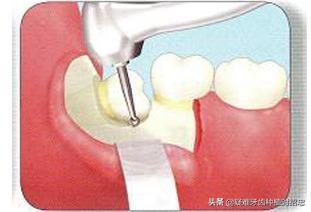

干槽症公认原因是拔智齿时创伤、伤口过大

,(比如上文所说的那样,拔牙时间过长,或为了更好的手术视野把牙龈切开,术后又缝合不理想等原因),

所引起的继发感染

。因此,为了预防干槽症的发生,在拔牙过程中应尽量减少创伤,拔牙后应尽量缩小拔牙创口;拔牙前后可以使用抗生素,预防感染。